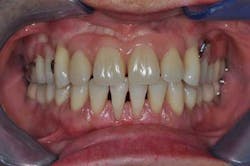

Figs. 9a, b, and c: Two years’ postop. Note the patient’s commitment to maintaining an optimal oral hygiene

- 2 years’ postop.